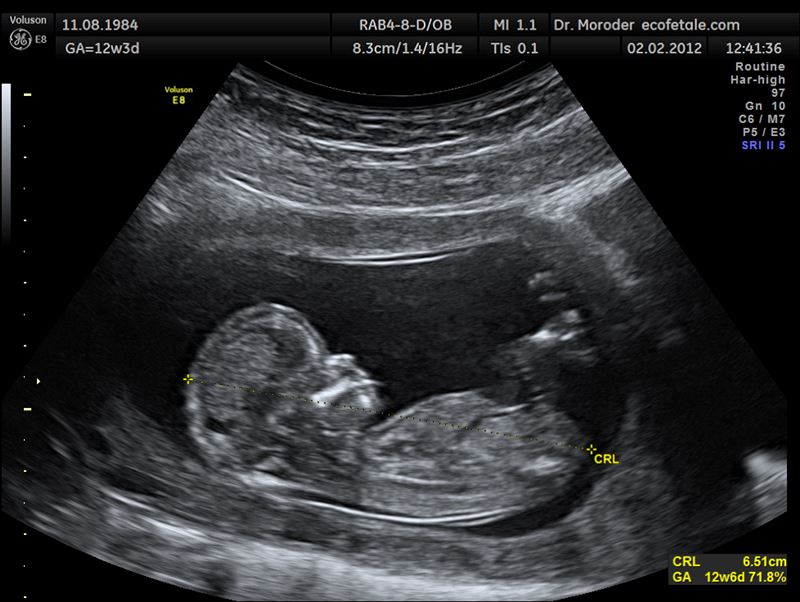

▼後來原po去做產檢照超音波,醫生告訴她肚子裡的是女孩,最後她果然生下一個女寶。她想起當初學生們的話,非常好奇,為什麼小孩子一開始就知道?難道他們真的看到了什麼?原po上網求助,想看看網友們的說法。